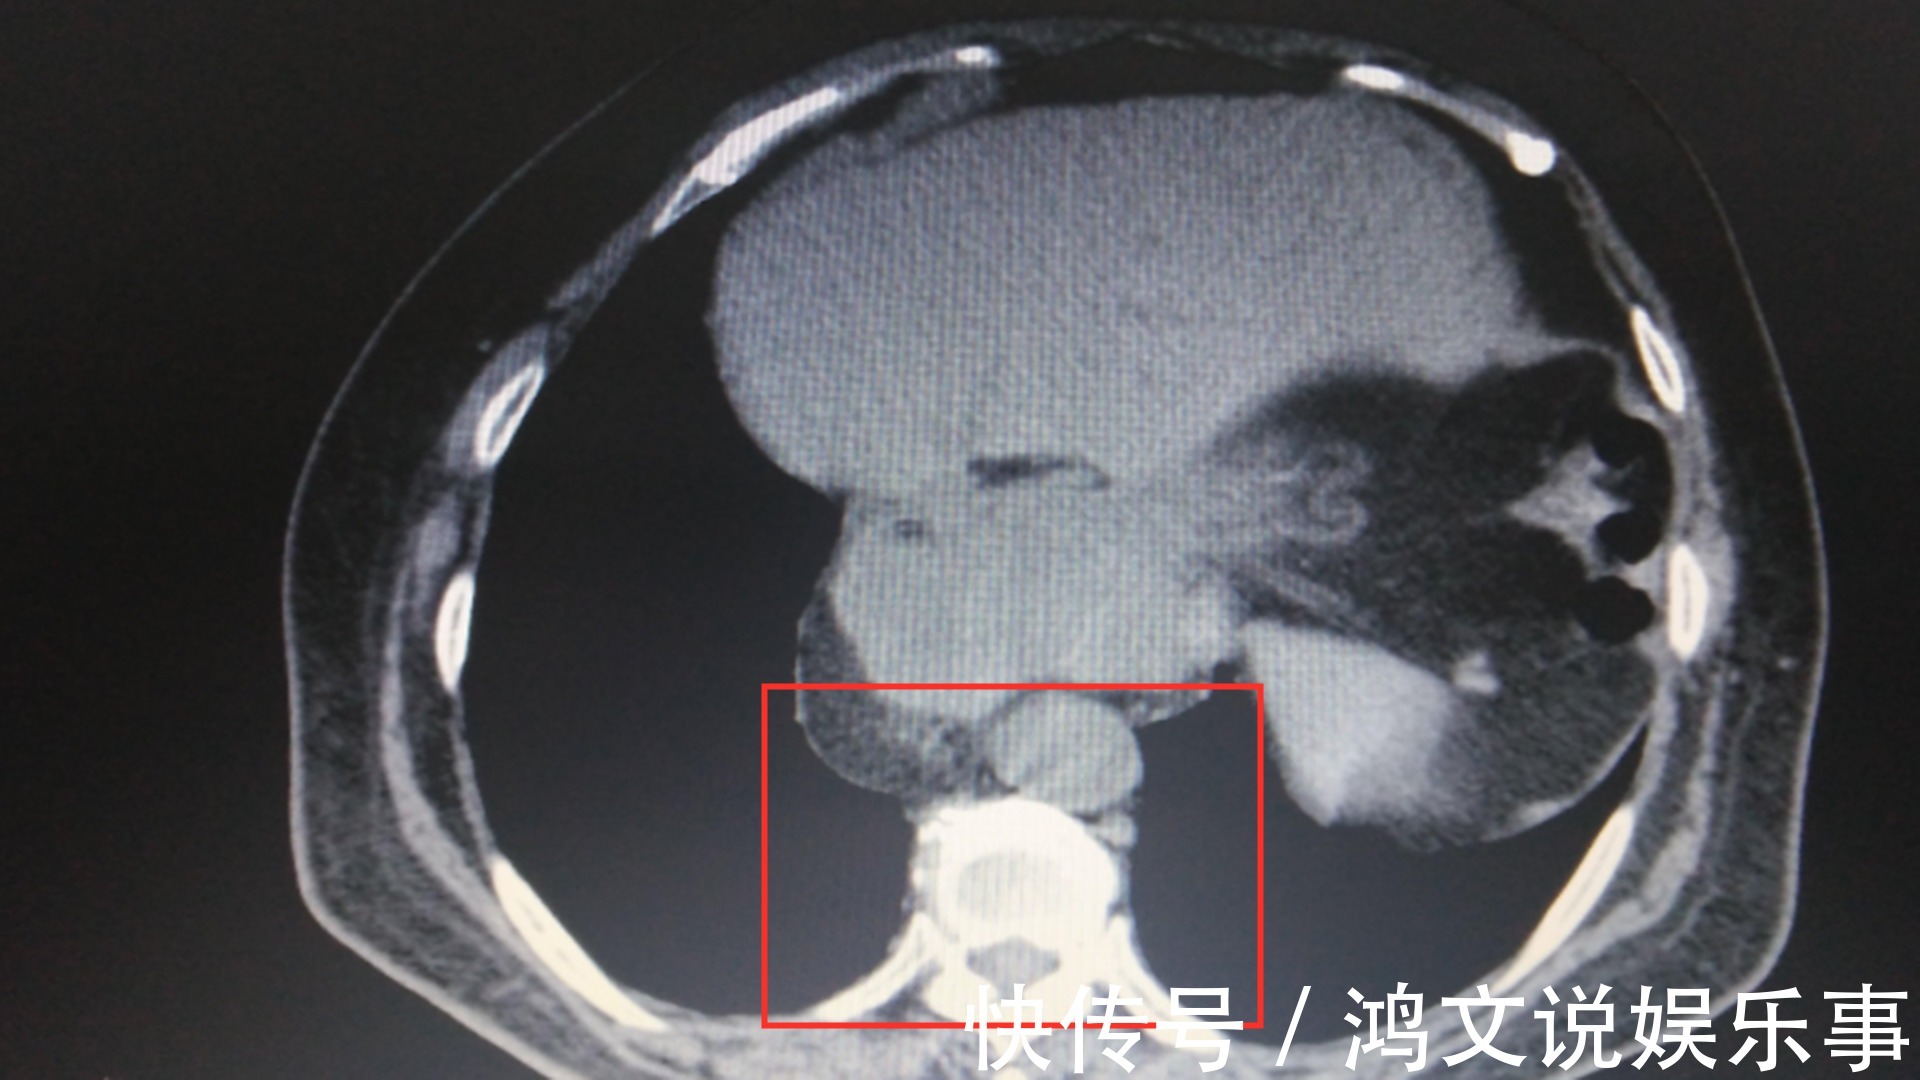

最终经过多项检查,发现原来孩子的中腹胃粘膜异位了,这里必须给大家普及一下,这个中腹胃粘膜异位的情况,其实是先天性的一种消化道畸形,最常见的一种表现,就是肠道胃壁出现薄弱区,发生这种先天性疾病的几率一般在1%-3%左右,但是我们也需要知道有这样的事情存在。如果小孩子也如同这位女童一样出现了以外出血的情况,我们要及时送院治疗,这位女孩是在第二天才送院的,其实个人建议一旦出现了便血的情况,最好当天就到医院进行诊断,特别是出血量特别巨大的情况,一定要及时到医院进行诊断,以免耽误了病情。

孩子最终进行了手术治疗,术后恢复的情况还是不错的,大家不用太过担心,但是在手术过程当中,找出出血点的过程却是不易,但最终在医生的努力下,终于找到了出血点,而大出血的最终原因是因为一条粗血管被胃酸腐蚀掉了,所以孩子就发生了大出血的情况。手术修复了右侧的斜疝,切掉了憩室,让大出血的症状得到了很好的控制,让孩子脱离了生命危险,如果顺利的话,大约在6月10日孩子就可以康复出院了。